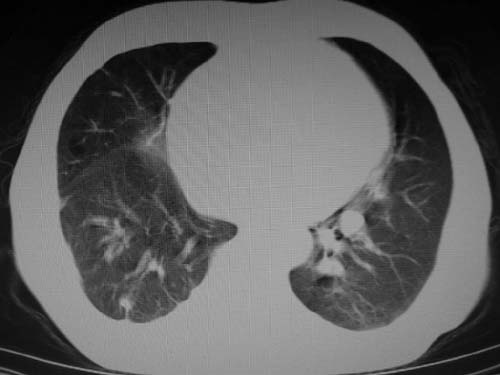

男,80岁

肺a高压征[左肺a狭窄?];肺,胸膜tb

右肺上叶结核;左肺门占位?建议增强扫描.

左下肺静脉扩张,原因?建议cta

左肺动脉异常增粗,建议增强。

1)考虑肺动脉狭窄。2)右肺上叶继发性肺结核。3)右侧胸膜增厚、钙化,左侧胸膜反应。

肺动脉瘤。建议先行ct增强扫描

左肺动脉异常增粗,考虑肺动脉狭窄可能。

右肺上叶继发性肺结核。

右侧胸膜增厚、钙化,左侧胸膜反应。

左肺动脉异常增粗,建议ct增强,排除肺门肿瘤

右侧胸膜增厚、钙化,左侧胸膜反应

1)考虑左肺动脉瘤可能性大,建议增强。2)右肺上叶继发性肺结核。3)右侧胸膜增厚、钙化,左侧胸膜反应。

肺动脉段突出,左右肺门不等大,左肺门明显增大,肺动脉干及左肺动脉明显增宽,考虑先天性肺动脉狭窄瓣膜狭窄型。

)考虑肺动脉扩张,右心室增大,主动脉弓段正常位弓后段明显变小(不会是动脉导客未闭吧,不知患者有何症状病史)0。2)右肺上叶继发性肺结核。3)右侧胸膜增厚、钙化,左侧胸膜反应。

右肺上叶尖段结核;左肺下叶占位?建议增强扫描。右侧胸膜增厚;右肺局限性肺气肿。

肺动脉高压,左肺动脉瘤样扩张。